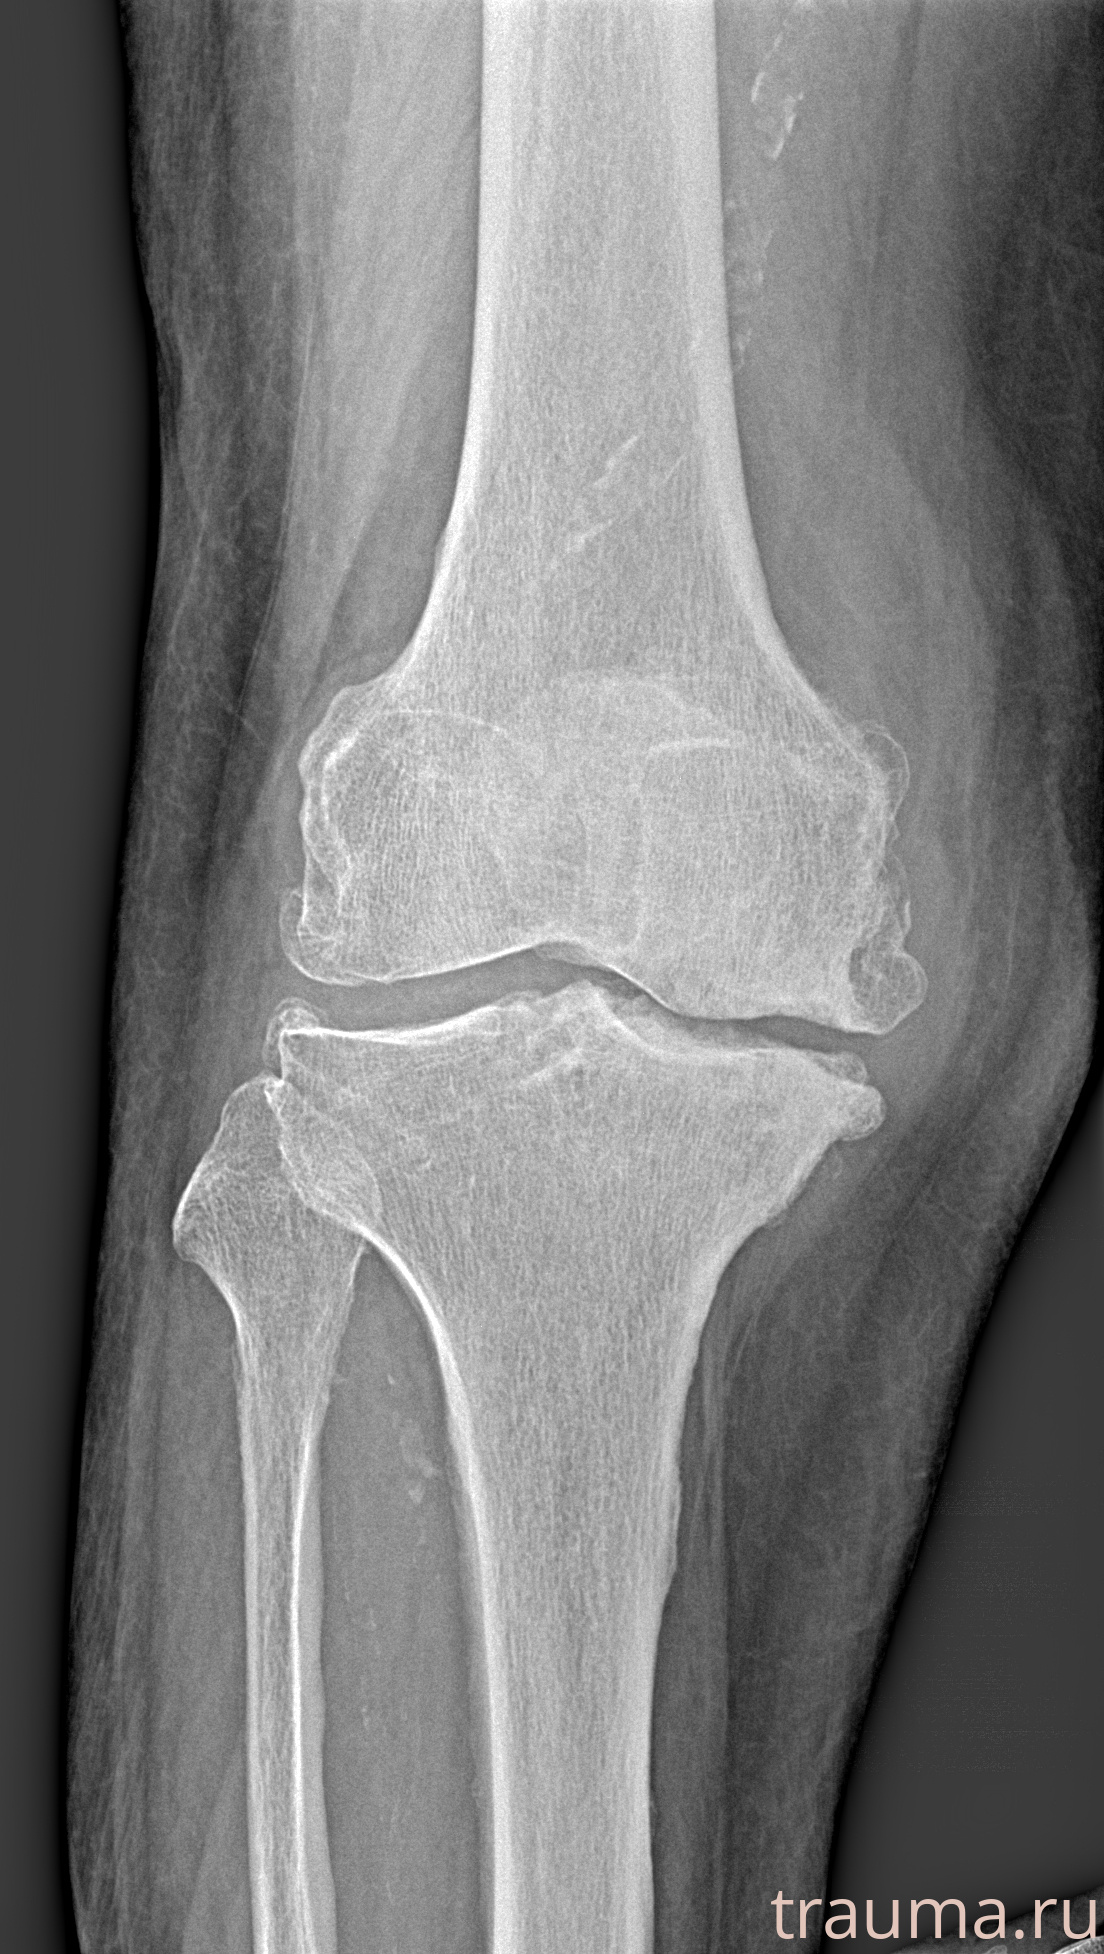

Рентгенограммы